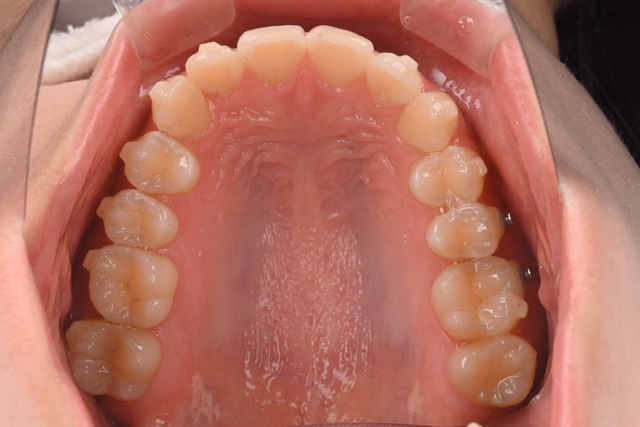

骨格分析に基づき、欠損部にインプラントを入れず、インビザライン(マウスピース矯正)でスペースを閉鎖しながら歯並びと咬合を同時に改善しました。

他院で「インプラントは難しい」と説明を受けた20代女性から、インプラント希望でご相談。精査の結果、矯正でのスペース閉鎖が適応と判断しました。

- 診断:CBCT・口腔内スキャン・咬合解析で移動量と方向を定量化

- 設計:IPR+アタッチメントでミリ単位に歯を再配置

- 結果:スペース閉鎖+配列改善により、見た目・発音・咬合安定・清掃性が向上